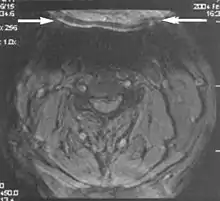

Metal artifacts

Metal artifacts occur at interfaces of tissues with different magnetic susceptibilities, which cause local magnetic fields to distort the external magnetic field. This distortion changes the precession frequency in the tissue leading to spatial mismapping of information. The degree of distortion depends on the type of metal (stainless steel having a greater distorting effect than titanium alloy), the type of interface (most striking effect at soft tissue-metal interfaces), pulse sequence and imaging parameters. Metal artifacts are caused by external ferromagnetics such as cobalt containing make-up, internal ferromagnetics such as surgical clips, spinal hardware and other orthopaedic devices, and in some cases, metallic objects swallowed by people with pica.[3] Manifestation of these artifacts is variable, including total signal loss, peripheral high signal and image distortion (Figs 3 and 4).[1] Reduction of these artifacts can be attempted by orientating the long axis of an implant or device parallel to the long axis of the external magnetic field, possible with mobile extremity imaging and an open magnet. Further methods used are choosing the appropriate frequency encoding direction, since metal artifacts are most pronounced in this direction, using smaller voxel sizes, fast imaging sequences, increased readout bandwidth and avoiding gradient-echo imaging when metal is present. A technique called MARS (metal artifact reduction sequence) applies an additional gradient, along the slice select gradient at the time the frequency encoding gradient is applied. ==Signal processing dependent artifacts== The ways in which the data are sampled, processed and mapped out on the image matrix manifest these artifacts.[1]